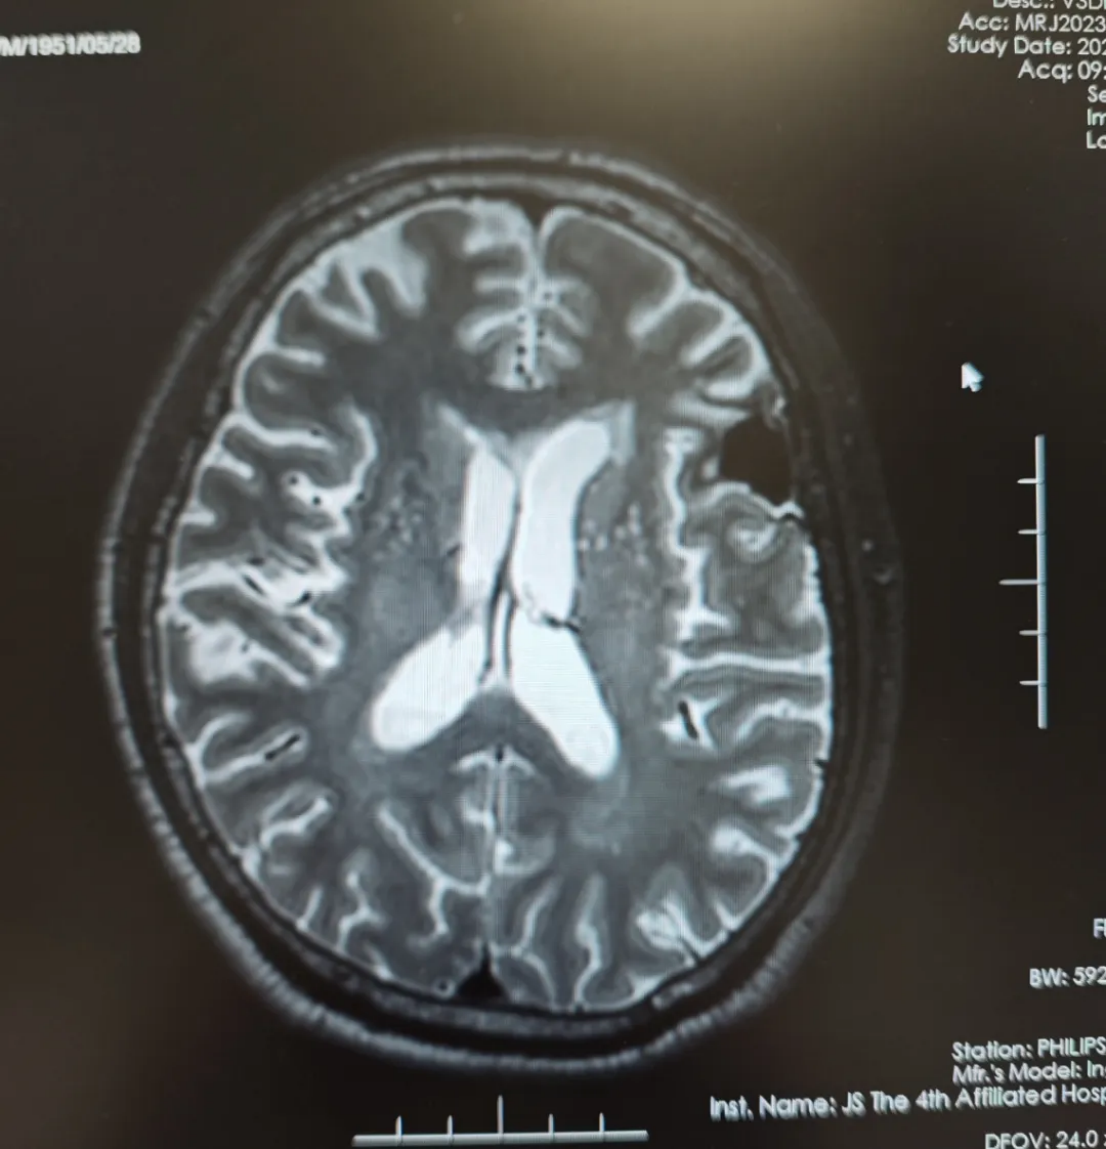

2023-12-15化疗4周期后复查头颅磁共振平扫提示:

左侧额叶转移瘤治疗后复查,较前片(2023-10-12)病灶及周围水肿明显缩小;两侧额叶及放射冠区少许缺血灶;老年性脑改变(图3)。

图3 化疗4周期后复查头颅磁共振平扫